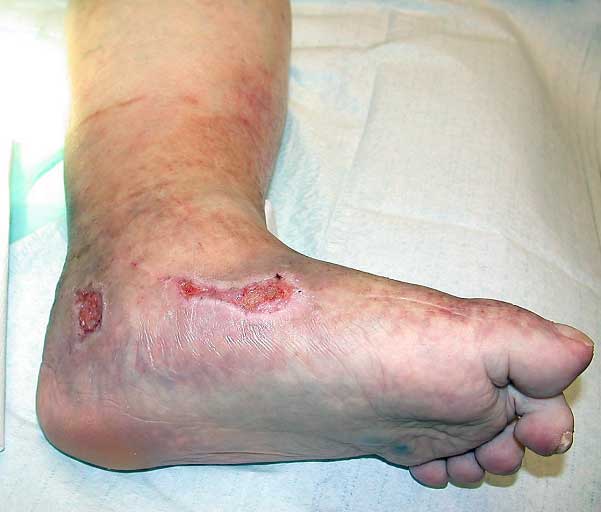

- 13–26 %:ssa tapauksista syynä on laskimovajaatoiminta yhdessä samanaikaisesti esiintyvän valtimoverenkierron vajauksen kanssa (ns. kombinoitunut valtimo-laskimohaava tai sekahaava) «Kombinoitunut valtimo-laskimohaava (ns. sekahaava) sääressä»1, «Körber A, Klode J, Al-Benna S ym. Etiology of chro...»13, «Jockenhöfer F, Gollnick H, Herberger K ym. Aetiolo...»15, «Hedayati N, Carson JG, Chi YW ym. Management of mi...»16.

Kombinoitunut valtimo-laskimohaava (ns. sekahaava) sääressä.

kuva: PSHP kuva-arkisto